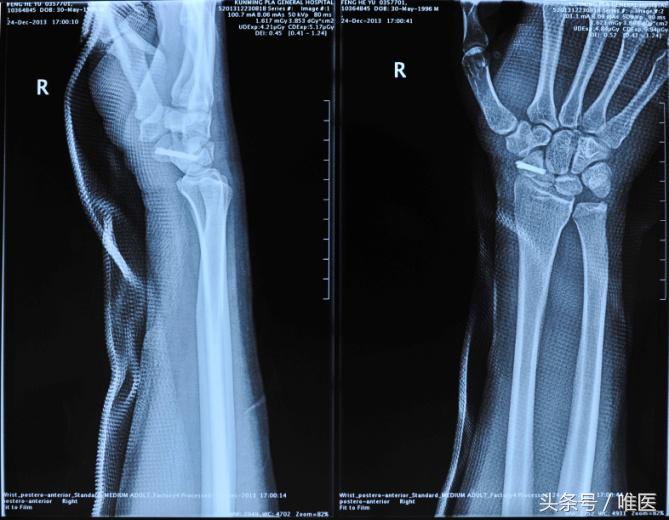

2.Herbert螺钉+辅助克氏针内固定

该术式是近年来许多临床医师尝试的一种新方法,并且取得了较好的成效,Hiren和Jeon等已较完善的阐明了可根据舟骨骨折的位置选择正确的术式,并且证实影像学监控下将螺钉置于中央区域、选择尽量长的螺钉、固定效果最佳,全螺纹螺钉生物效能最佳。临床上对于新鲜的经舟骨月骨周围脱位的患者应用此方法较为广泛,但Herbert螺钉固定方法学习曲线较长,对于临床经验和医疗设备上要求较高。